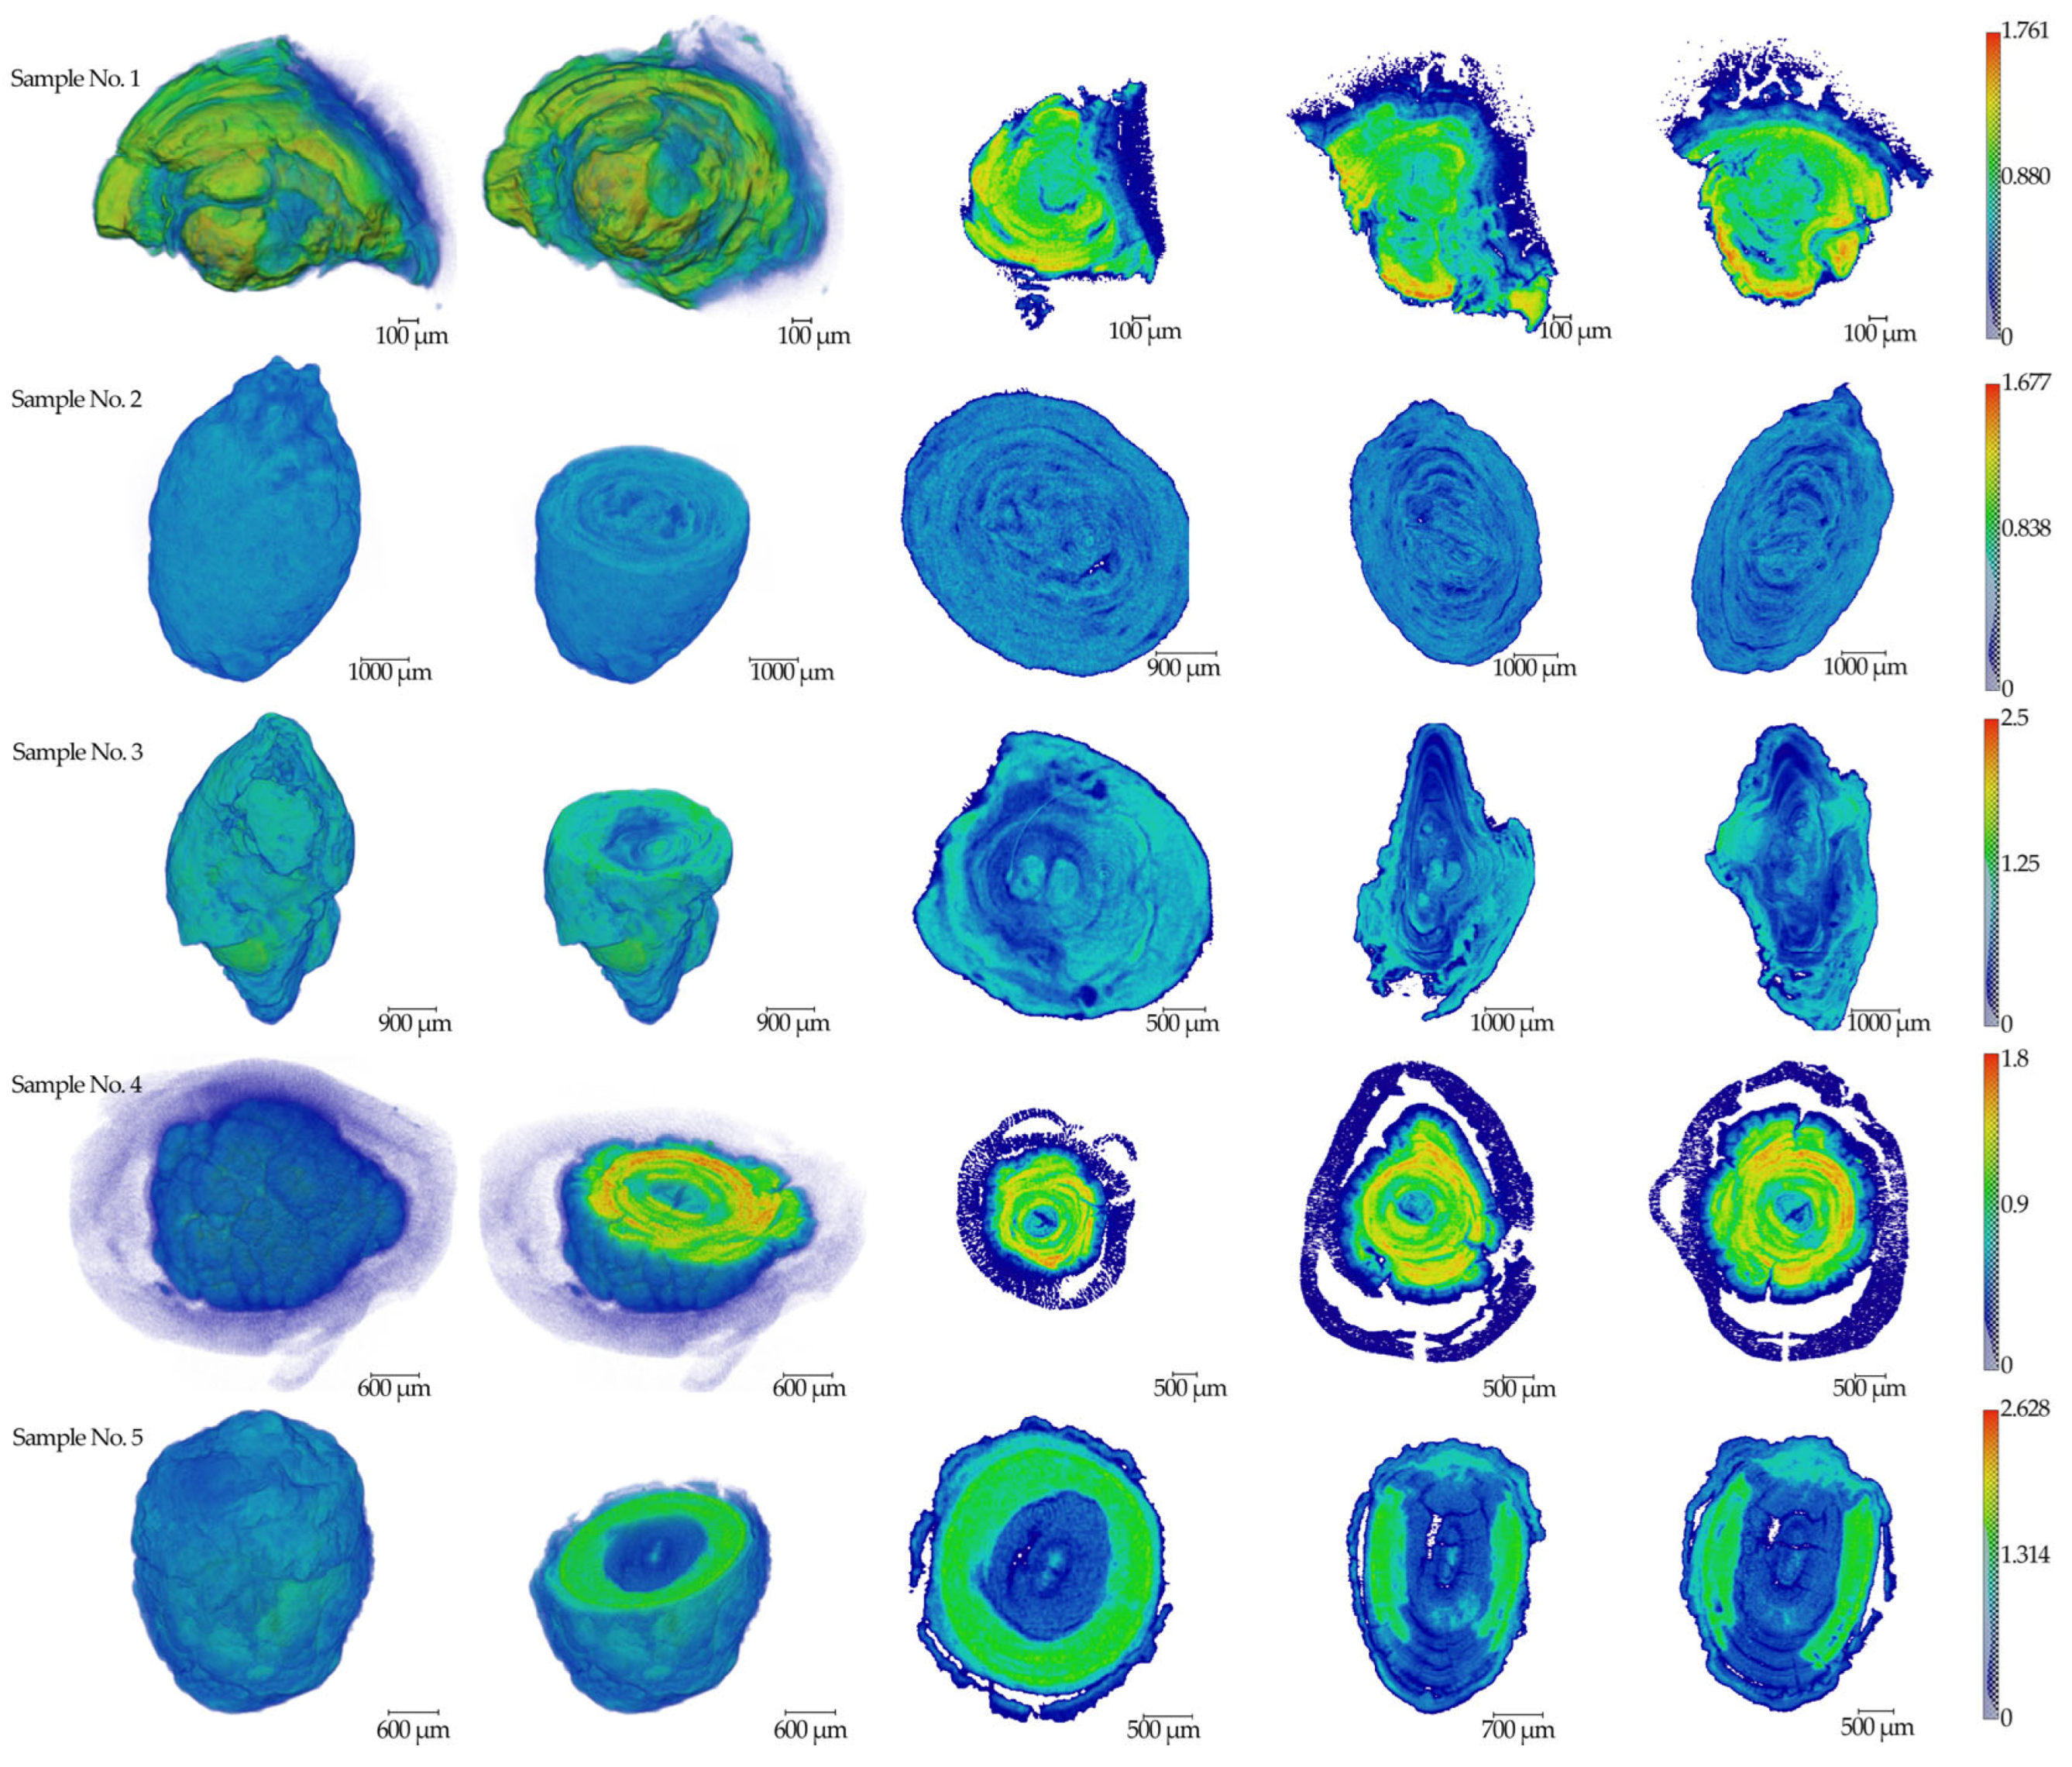

2.1. The Results of X-ray Studies of Salivary Gland Stones

4.2. X-ray Micro-CT

4.3. X-ray Fluorescence Analysis (XRF)